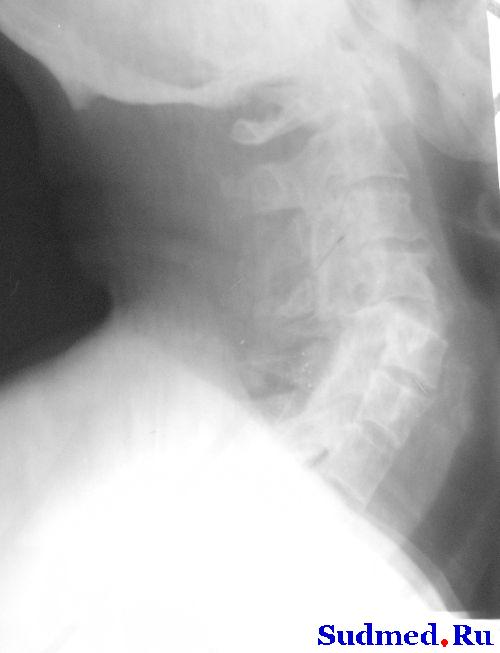

описание снимков такое : На рентгенограммах шейного отдела позвоночника в 2-х проекциях определяется вывих С4 кзади на ½ диаметра тела позвонка, со сдавлением позвоночного канала на ¾ диаметра. Признаки остеохондроза шейного отдела позвоночника С2-С3, С№-С4, С4-С5, С 5-С6 2 степени.

рентген, наконец-то выложил

Эскизы прикрепленных изображений

Судебная медицина - Прикрепленное изображение

с меньшими шумами

Судебная медицина - Прикрепленное изображение Судебная медицина - Прикрепленное изображение